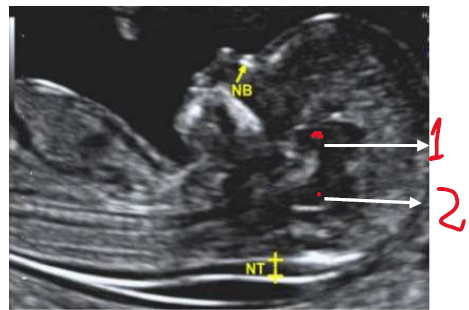

Em relação ao exame obstétrico do primeiro trimestre, podemos afirmar:

I - A mensuração da transluscência nucal é realizada em corte transversal, com o feto em posição neutra.

II - A medida do CCN (comprimento cabeçanádegas) deve estar entre 45-90 mm para realização da avaliação morfológica do 1º trimestre.

III - As estruturas assinaladas na imagem abaixo, correspondem ao diencéfalo (1) e ao tronco cerebral/ponte e bulbo (2).

IV - A imagem deve estar ampliada de maneira que apenas a cabeça e a parte superior do tórax sejam vistas.